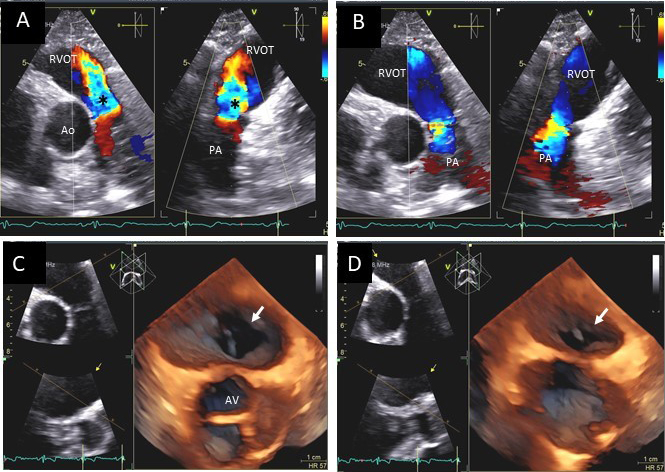

Severe PR also causes RV dilatation and diastolic flattening of the interventricular septum due to volume overload. A normal RV size suggests the absence of chronic severe PR. Carcinoid disease causes thickening and restriction of tricuspid and pulmonic valves leading to valve stenosis and regurgitation. This leads to turbulent forward flow in systole due to varying degrees of pulmonic stenosis and regurgitation due to incomplete closure of the thickened and restricted valve leaflets (Fig. 12).

Fig. 12.Pulmonic valve regurgitation and stenosis. Transthoracic echocardiographic images in a patient with carcinoid syndrome involving the pulmonic valve. Short axis biplane color Doppler views at the cardiac base showing severe pulmonic insufficiency (black asterisks - (A) and turbulent forward flow in systole due to pulmonic stenosis in (B). Three dimensional transthoracic views showing diffusely thickened and restricted pulmonic valve leaflets in systole (white arrow - (C)) and incomplete closure of the thickened pulmonic valve leaflets in diastole (white arrow - (D)) causing severe pulmonic regurgitation.